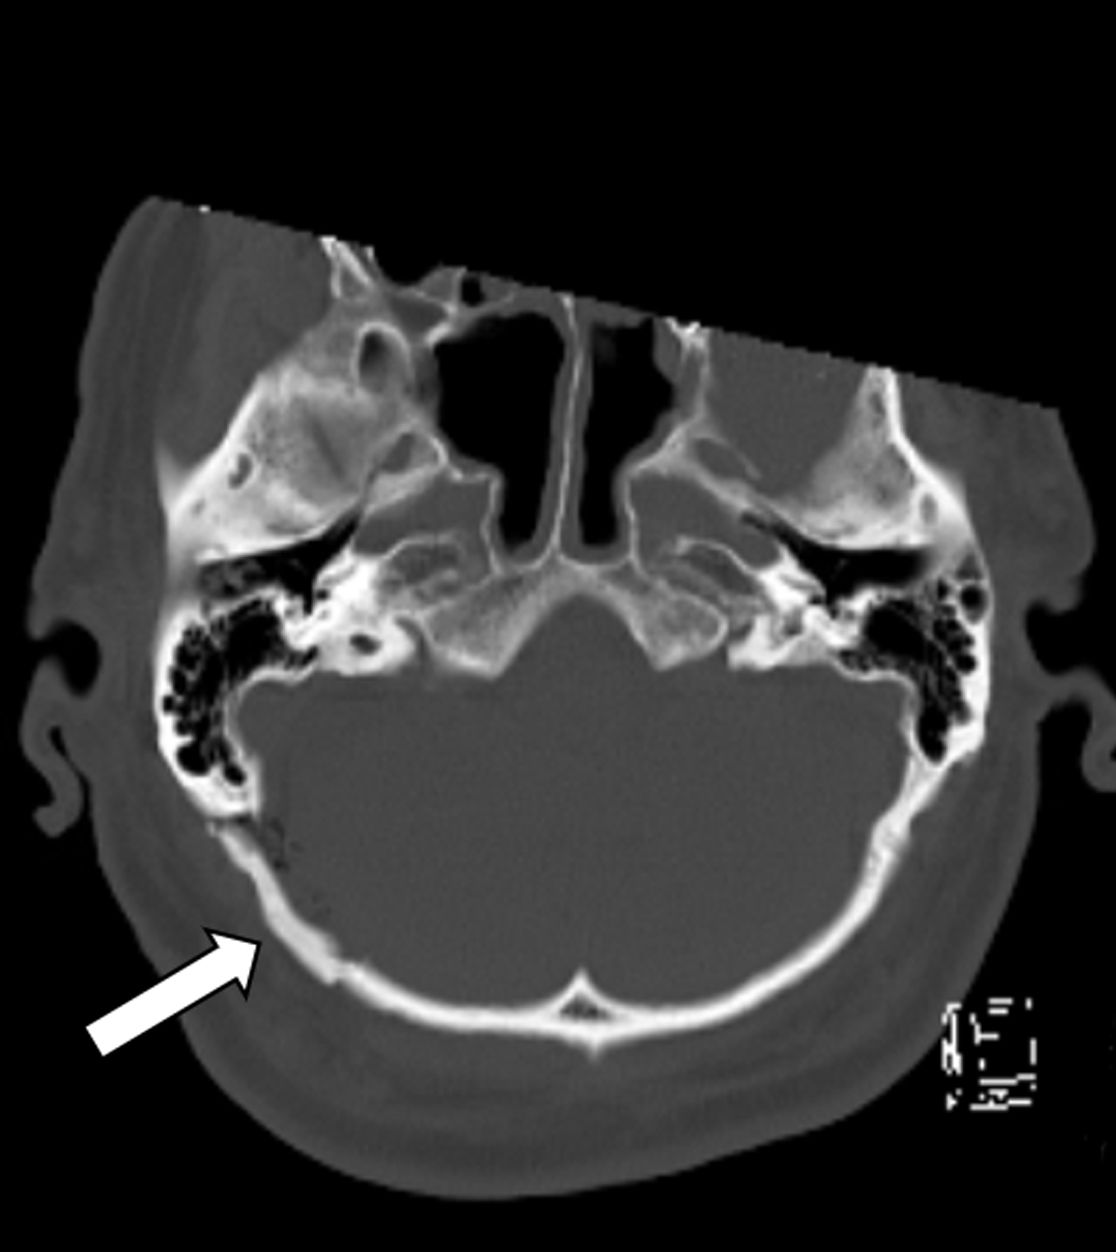

Liegt bei einer Trigeminusneuralgie eine Gefäßschlinge vor, welche den Trigeminusnerv berührt, kann bei unzureichender Linderung durch eine medikamentöse Therapie ggf. durch eine operative Lösung von Nerv und Gefäß eine Schmerzreduktion erreicht werden. Hierfür wird der Trigeminusnerv an seiner Eintrittsstelle zum Hirnstamm aufgesucht und durch z.B. ein Teflon-Stück vom Gefäß getrennt.

Gefäß-Nerven-Kontakt im Bereich des Nervus trigeminus (Pfeil)

Status nach mikrovaskulärer Dekompression über einen Zugang hinter dem Ohr (Pfeil)